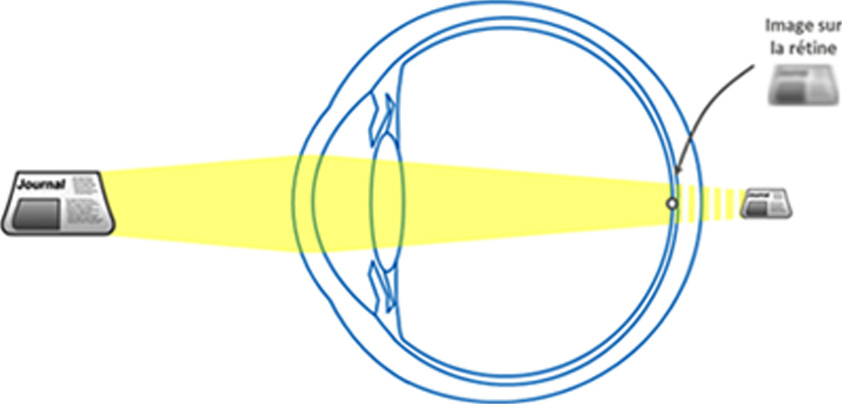

En effet, si l'oeil était statique, l'emmétrope (c'est-à-dire une personne sans défaut de vision) ne pourrait voir net que de loin car les images des objets proches se formeraient en arrière de la rétine et apparaîtraient donc floues.

En augmentant sa puissance, le cristallin permet de corriger cela en ramenant l'image de l'objet sur la rétine.